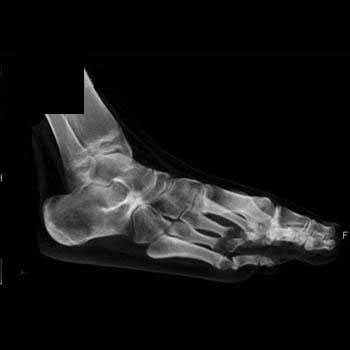

If suspected, imaging begins with conventional radiographs. Three views of the foot are necessary, as the oblique view is best for detecting calcaneonavicular and talonavicular coalitions. However, talocalcaneal coalitions are not as reliably diagnosed with conventional radiographs, and often require CT or MRI to detect. CT is helpful in any type of coalition to elucidate whether the union is osseous, fibrous or cartilaginous, to detect secondary OA, and for preoperative determination of the extent of joint involvement and the appropriate type of surgical treatment. Postoperatively, CT can confirm whether a coalition has recurred or detect secondary osteoarthritis.

Calcaneonavicular coalitions are generally seen on 45 degree oblique conventional radiographs. An osseous bar between the calcaneus and navicular may be evident, or the two bones may be in close proximity. A secondary sign is hypoplasia of the talar head (4). The axial orientation is the best plane with which to evaluate calcaneonavicular coalitions using CT. Again, if the coalition is not entirely bony, the primary finding may be a narrowing of the space between the 2 bones.

A number of secondary findings have been described using conventional radiographs to detect talocalcaneal coalitions. These include a talar beak at the insertion of the talonavicular ligament, a narrowed posterior subtalar joint, the inability to visualize the middle subtalar joint on the lateral film, broadening of the lateral process of the talus, narrowing of the posterior subtalar joint, among other findings. In addition, Lateur described the “C sign”. This is a reverted C visible along the posterior foot, from the talar dome (superior to posterior), along the posterior talocalcaneal joint, to the sustentaculum tali (inferiorly). This was previously believed to be a reliable sign on conventional radiography, evident in 87-98% of lateral radiographs in the setting of talocalcaneal coalition. Recently, lateral radiographs were correlated with CT and surgery to determine the sensitivity and specificity of this sign. This new data revealed that the “C sign” is only 49% sensitive, but 91% specific for talocalcaneal coalition. One additional finding associated with this type of coalition, irregularity of the posterior talocalcaneal joint, was shown to be 71% sensitive and 93% specific for talocalcaneal coalition. The authors concluded that the C sign was only reliable if the coalition was large or the bones were mature . This new data supports the importance of MDCT if the diagnosis is suspected but the conventional radiograph does not depict the coalition.